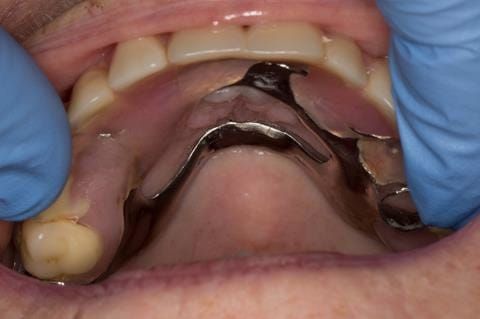

- Poorly fitting cobalt chromium based maxillary partial denture, which has been added to. This exhibited poor retention, stability and tissue fit (support). Unable to wear a new acrylic based denture.

- Cobalt chromium reinforced gasket denture - using a Molloplast B "O" ring to retain and stabilise the denture. This was my professional preference as this was the least invasive and simplest solution to this dental problem. Should the UR7 require removal in the future - an artificial tooth could be added - resulting in a complete denture. The patient would have adapted to the denture fully by this stage and have good neuromuscular control of the prosthesis.

Following consultation and second discussion appointment the patient chose to have option 2 namely, a window denture - maxillary cobalt chromium based partial denture. The clinical situation and treatment process is shown in detail below with photographs. The patient was successfully rehabilitated with this and her quality of life considerably improved. The clinical work was provided by Finlay and the technical work by Rowan.